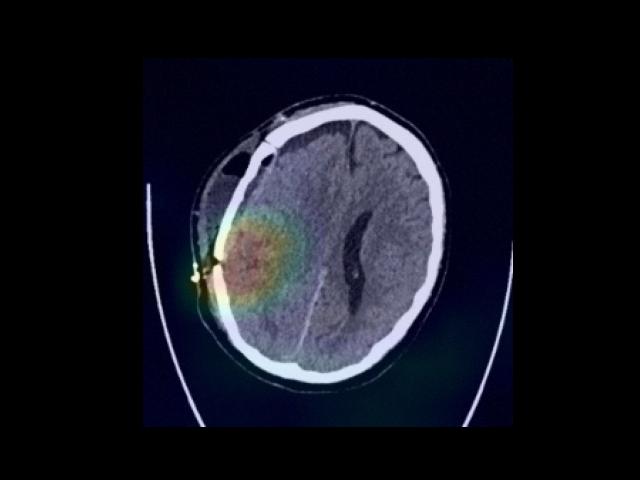

Sample Gallery